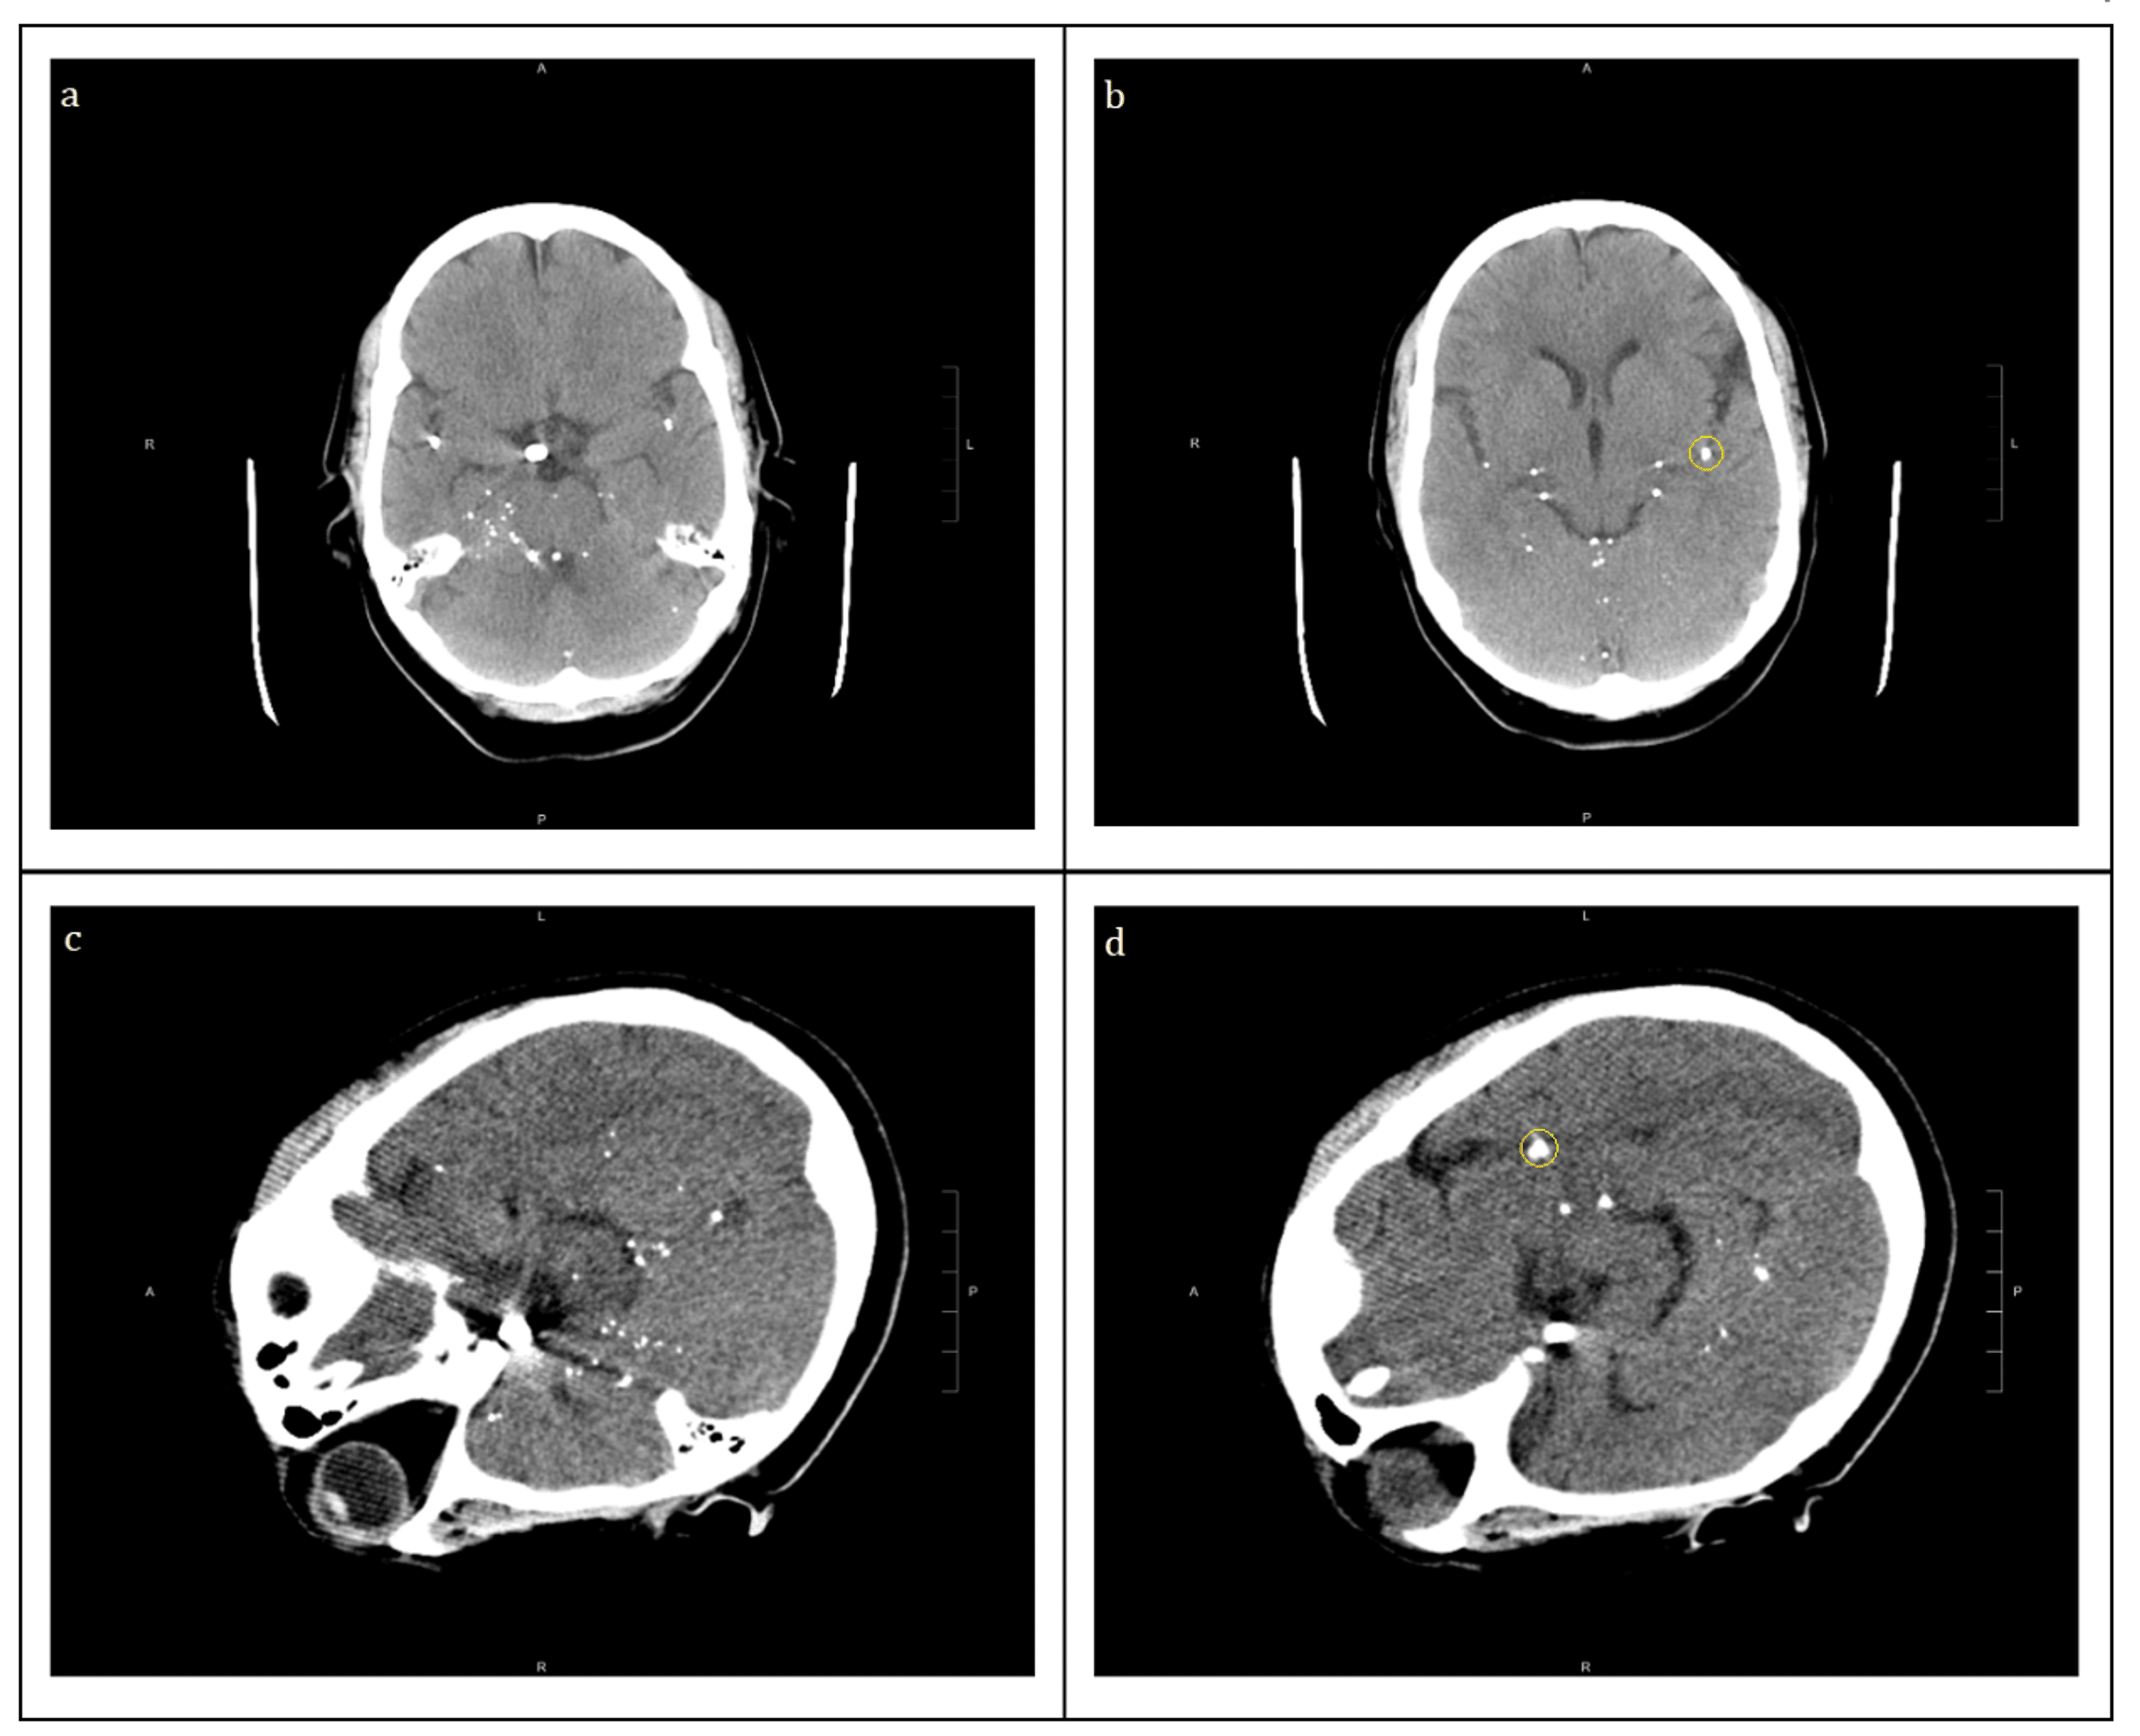

CT. CT is only rarely obtained, and usually when the diagnosis is unclear. Indeed, placing the child in the supine position can actually precipitate respiratory arrest. If a scan is obtained, marked edema and thickening of the epiglottis and aryepiglottic folds may be seen with narrowing of the airway. On lateral C-spine X-ray, the thumbprint sign describes a swollen, enlarged epiglottis. [10] A normal X-ray, however, does not exclude the diagnosis. [10] An ultrasound may be helpful if specific changes are present, but its use (as of 2018) is in the early stages of study. [10] On CT imaging, the "Halloween sign" describes an epiglottis of The thumb sign in epiglottitis is a manifestation of an edematous and enlarged epiglottis which is seen on lateral soft-tissue radiograph of the neck, and it suggests a diagnosis of acute infectious epiglottitis. This is the radiographic corollary of the omega sign 1-3. Thumb sign is a term also used in other conditions: Computed tomography (CT) scan in an adult with acute epiglottitis shows a column of air around the epiglottis (E). The right side is more swollen than the left, and the hypo-attenuating area (A) is suggestive of fluid or the early formation of an abscess. View Media Gallery. In addition to Hib, bacterial culprits include groups A beta-hemolytic Halloween sign: describes the CT appearance of a normal-thickness epiglottis Epiglottis A thin leaf-shaped cartilage that is covered with laryngeal mucosa and situated posterior to the root of the tongue and hyoid bone. During swallowing, the epiglottis folds back over the larynx inlet thus prevents foods from entering the airway. Obliteration of the vallecula (“vallecula sign”) may be seen (figure below, white arrow). Performance? ~88% sensitive, so a negative X-ray doesn't exclude epiglottitis. (27247205) neck CT scan. Roles of CT scan: [1] Diagnosis of epiglottitis. Contrasted CT scan of the neck has a sensitivity of 88-100% and specificity of ~96% for epiglottitis. The epiglottis is a single midline leaf-shaped fibrocartilaginous structure that forms part of the supraglottic larynx and defines the division of the hypopharynx from the larynx. It helps conduct food boluses from the oropharynx to esophagus, avoiding the food entry into the larynx 7. It is one of the 9 laryngeal cartilages. X-ray of the lateral soft tissue of the neck shows a swollen epiglottis and pre-vertebral soft-tissue swelling. direct laryngoscopy by an expert is however, the gold standard investigation.[30, 31] CT scan shows diffuse thickening of the epiglottis and AEFs. Laryngoscopic examination requires special training this facility is usually available Andr~ Lamothe, MD*. Rece~ved for publication April i9, 1996. Revisions received December 12, 1996, andJanuary 1 and 29, 1997. Accepted for publication February 4, 1997. DrH~bert is acareer scientist with the Ontario Ministry of Health. Presented in part a he1995 Canadian Society of Otolaryngology Annual Meeting held in St John, New Brunswick A contrasted Computer Tomography (CT) neck was performed in view of the protracted course of recovery. This revealed oedema of the epiglottis and aryepiglottic folds bilaterally, but no abscesses or abnormal masses were seen (Fig. 4). The patient was discharged on day 9 of admission after the scan. He was reviewed regularly in the outpatient It should be noted that an omega epiglottis, either a variant of normal or in the setting of laryngomalacia, can result in a similar appearance and can be mistaken for epiglottitis. In epiglottitis, the hypopharynx may be over-distended. CT. CT is only rarely obtained, and usually when the diagnosis is unclear. Safneck et al. (1993) reported a 13-year-old male with foreign body sensation and difficulty breathing while supine who underwent CT scan revealing a 2 cm mixed attenuation mass on the laryngeal surface of the epiglottis with subsequent excision yielding solitary fibrous tumor. 22 Neurogenic tumors such as schwannomas, neurofibromas, and Background Only about 1% of all head and neck lateral or paramedian cancers described in the scientific literature shows, in staging, contralateral cervical adenopathy without ipsilateral pathological involvement of lymph nodes. Case Presentation This case is one of them, in which 18F–FDG PET/CT scan is confirmed by pathology findings, and has correctly identified all metastatic disease foci We present a 65-year-old female with an incidental 1 cm exophytic, pedunculated, papillomatous lesion on the laryngeal surface of the epiglottis discovered upon endoscopic evaluation for dyspepsia and heartburn. Because of her risk factors for malignancy, CT scan was requested and revealed only benign features. Figure Figure1 1- -c: c: transaxial PET/CT scan shows an increased [18F]-FDG uptake area on the right versant of the epiglottis (white arrow); Fig. Fig.1 1- -d: d: transaxial PET/CT scan demonstrates clearly that right lateral cervical lymph nodes are not pathological (red arrow) and confirm, on the left side, the adenopathy (white arrow). It should be noted that an omega epiglottis, either a variant of normal or in the setting of laryngomalacia, can result in a similar appearance and can be mistaken for epiglottitis. In epiglottitis, the hypopharynx may be over-distended. CT. CT is only rarely obtained, and usually when the diagnosis is unclear. n January 2016 and October 2019. The diagnosis of acute epiglottitis was based on the clinical presentations and fiberoptic laryngoscopic examinations of the larynx and hypopharynx. Details of age, gender, personal history, clinical symptoms, treatment, and hospital stay were evaluated. Results: Out of the 28 patients with acute epiglottitis, 17 (60.71%) were male and 11 (39.29%) were female American Roentgen Ray Society Images of Epiglottitis CT scan All Images X-rays Echo & Ultrasound CT Images MRI; Ongoing Trials at Clinical Trials.gov. US National Guidelines Clearinghouse. NICE Guidance. FDA on Epiglottitis CT scan. CDC on Epiglottitis CT scan. Epiglottitis CT scan in the news. Blogs on Epiglottitis CT scan An imaging test: An X-ray or computerized tomography (CT) scan can sometimes identify a swollen epiglottis, which will appear on screen as a small wedge at the top of the throat. A throat culture: If the Hib bacterium is present, the medical team can identify it by wiping the epiglottis with a cotton swab and analyzing the sample in a lab. Epiglottitis is a medical emergency. If you or someone you know exhibits epiglottitis symptoms — such as difficulty breathing, difficulty swallowing, hoarseness or drooling — call 911 or head to your nearest emergency room. At the hospital, healthcare providers will begin epiglottitis treatment: